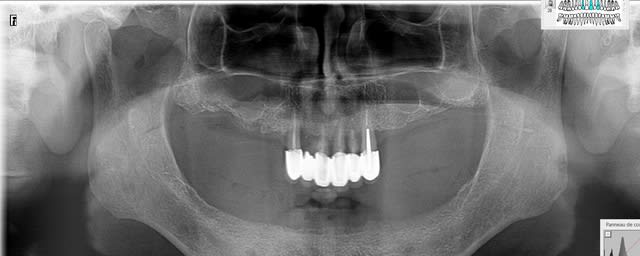

Panoramique dahmadi syqsnx - Eugenol